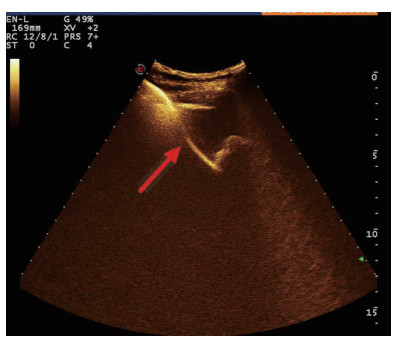

1.3 手术过程 1.3.1术前经肘静脉超声造影:行PTGBD前半h经肘静脉快速团注SonoVuel 5 mL,在对比脉冲序列造影成像模式下进行观察,根据不同组织造影剂凝聚的时间及浓度差异,判断胆囊周围组织黏连程度、胆囊壁完整程度(图 1),如出现胆囊壁造影剂充盈缺损(图 2、3),则考虑胆囊壁坏死或穿孔,根据静脉造影情况选择合适的置管入路,避开胆囊穿孔的部位及黏连组织。

| 图 1 经肘静脉超声造影胆囊图像,造影图(左),二维超声图(右) |

超声造影是利用超声造影剂微泡(本组应用的是声诺维超声造影剂微泡)在低机械指数声波照射下发生共振,产生线性及非线性谐波回声信号,形成造影增强图像的技术,是近年来新兴的超声技术,具有实时、可连续观察、无辐射、可重复性好、毒不良反应少等优势,为临床提供了全新的诊疗手段[14]。经肘静脉注入的标准配置超声造影剂是一种血池造影剂,可以反映组织的血流灌注情况同时亦被广泛应用于肝、脾、肾等实质性脏器破裂的诊断,其诊断的敏感性及特异性均明显优于二维超声,且与增强CT有较好的一致性[15-16]。本组病例术前经肘静脉注入标准配置造影剂后,胆囊壁均显影增强,胆囊穿孔及周边积液处表现为造影无充盈区,穿刺置管后再次静脉路超声造影,迅速发现术后出血部位且可敏感评估是否为活动性出血(经手术证实)。除1例因活动性出血中转腹腔镜手术外,其余32例置管成功后经引流管口注入稀释造影剂20 mL(1:200稀释),评价引流管位置、引流范围及是否出现胆汁外漏取得良好效果,所有引流导管均能够清晰显示引流导管置入路径、引流管形态及引流范围,引流管置入恰当者,头端位于胆囊内,全管显影清晰,造影剂弥散区域与胆囊大小吻合; 置管后胆汁漏出者,可见造影剂沿引流管周边渗出[17-18],本组中3例出现造影剂外渗,其中两例渗出范围局限于胆囊床附近,未渗出至游离腹腔,患者腹痛症状稍有加剧,经胆囊减压及对症处理后好转,其中1例见造影剂渗出至肝肾间隙,患者腹痛症状加剧明显,考虑置管位置不当,余行急诊腹腔镜手术治疗,术中证实为系膜胆囊,且可见引流管侧孔部分外露。笔者的经验是,术前选择静脉路超声造影有助于对胆囊情况的评估及穿刺点的选择,术中正确选择穿刺针的入路有利于提高穿刺引流的成功率。首先是胆囊穿刺部位的选择应选择在靠近胆囊颈侧,此处胆囊位置比较固定,受体位影响较小,且胆囊床结缔组织较为固定,有助于将漏出胆汁包裹局限,其次是进针方向与胆囊床尽可能保持垂直,减少进针位置的偏移,同时置管成功后应即刻尽量抽尽胆囊内的感染性胆汁,生理盐水冲洗后行经引流管稀释超声造影有助于判断置管位置、引流范围及是否出现胆汁漏出,减少不必要的并发症发生率。穿刺引流后可以根据患者的营养状况待窦道形成稳定后择期拔除引流导管。对全身情况改善适合手术治疗且有手术意愿者可以考虑择期胆囊切除术。